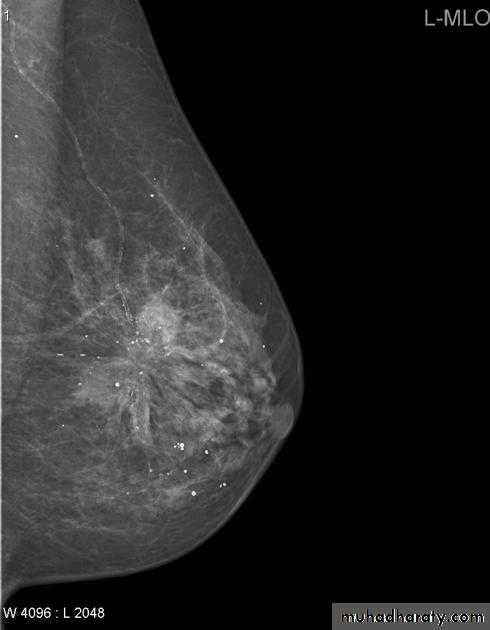

The mediolateral oblique (MLO) view is one of standard mammographic views. It is the most important projection as it allows to depict most breast tissue.

Mammography

The sensitivity of mammography for the detection of ILC reportedly ranges between 55-80% 8. Because of the limitations of mammography in detecting ILC, other modalities, such as sonography and MR imaging, are being used in evaluating clinically suspicious findings and known cancers to assess the extent of disease. ILC are more commonly seen on the craniocaudal (CC), compared to the mediolateral oblique (MLO).